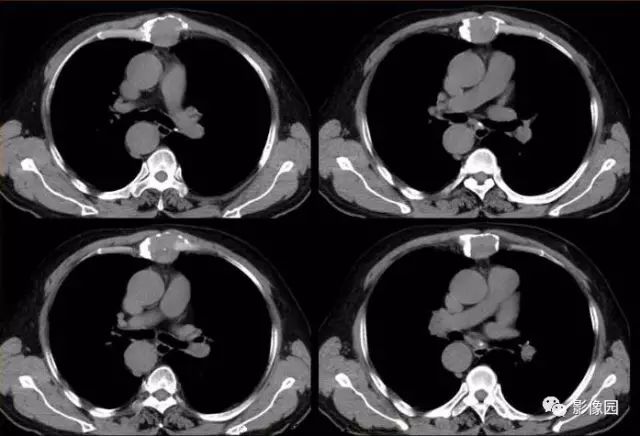

胸骨浆细胞骨髓瘤1例CT影像表现

【基本资料】男,66岁

【主诉】发现胸骨隆起1年余

【现病史】患者于1年前发现胸骨局部隆起,无红肿热痛,当时未予治疗,近来自觉隆起明显增大,伴胸前区隐痛不适。

【专科检查】胸骨上段局部隆起,压痛明显,胸部呼吸运动正常

肚肚丫头: 胸骨体局部呈膨胀性骨质吸收破坏,内呈软组织密度影,可见点状钙化,增强扫描呈轻度强化,周围软组织略肿胀。考虑:1.骨巨细胞瘤;2.浆细胞瘤;3.嗜酸性肉芽肿

【病理结果】(胸骨占位)符合浆细胞骨髓瘤

CT表现:特征性穿凿状、鼠咬状及蜂窝状骨破坏,边缘清楚,骨质疏松,病理性骨折及软组织肿块等表现,骨质硬化及骨膜反应少见。

骨破坏区完全为软组织取代,骨质膨胀,边界清楚,常突破骨皮质形成软组织肿块。增强扫描可见病灶轻中度强化,一般于静脉期达峰值。